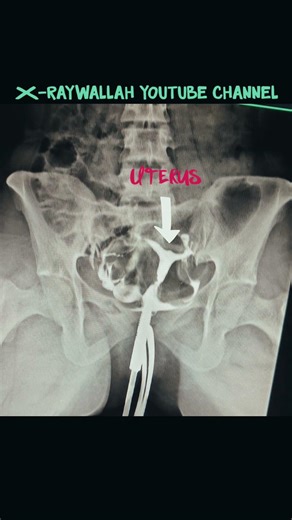

🩻 Hysterosalpingography (HSG) – Normal Study 🩺✨ This fluoroscopic image demonstrates a normal HSG examination, where contrast outlines the uterine cavity, bilateral fallopian

Radiology buzz. YGD Beats · NUCLEAR. 🩻 Hysterosalpingography (HSG) – Normal Study 🩺 This fluoroscopic image demonstrates a normal HSG examination, where contrast outlines the uterine cavity, bilateral fallopian tubes, and shows free peritoneal spill of dye, confirming tubal patency. 🔍 Key Radiological Findings: 🟢 Well-opacified ...

HSG PROCEDURE finding description check

YouTube

X-ray wallah